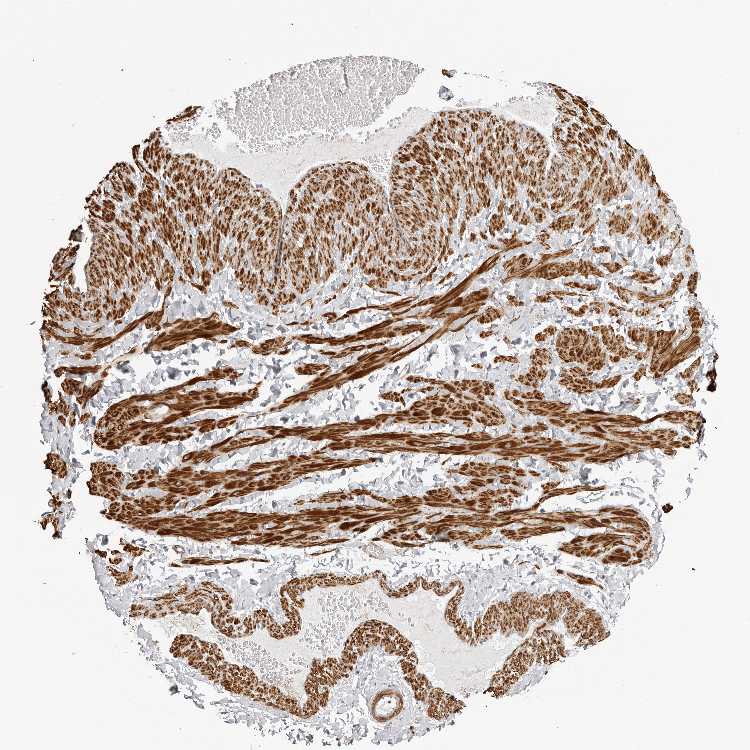

SOFT TISSUE 2 - Antibody stainingi

Antibody staining in the annotated cell types in the current human tissue is reported as not detected, low, medium, or high, based on conventional immunohistochemistry profiling in selected tissues. This score is based on the combination of the staining intensity and fraction of stained cells.

Each image is clickable and will lead to virtual microscopy that enables deeper exploration of all samples and also displays staining intensity scores, fraction scores and subcellular localization as well as patient and tissue information for each sample.

Antibody HPA023636Antibody HPA027962

Chondrocytes -Not detected

Fibroblasts Not detectedNot detected

Peripheral nerve LowNot detected